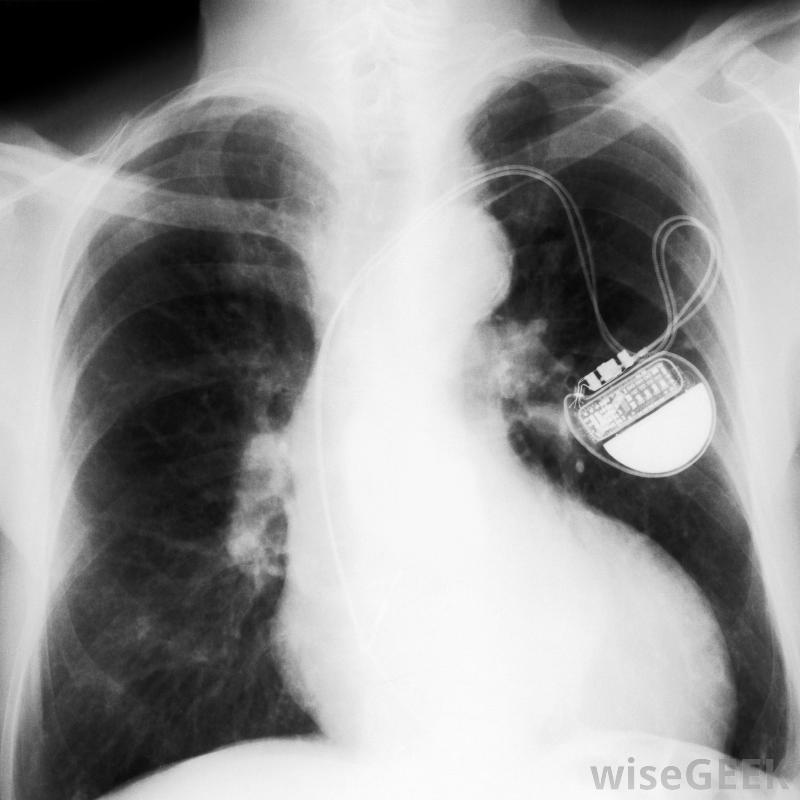

如何避免常見的起搏器問題(Avoid Common Pacemaker Problems)?

有很多方法可以避免心臟起搏器的問題,其中包括遵循醫生提供的定期維護計劃,包括電話隨訪和定期的醫生預約。你也可以避免暴露在發射強磁場的設備中,包括一些類型的焊接設備。采取特殊的預防措施進行磁共振成像(MRIs)也可能有幫助。有趣的是,即使把手機放在襯衫口袋里也可以幫助你避免起搏器問題一些心律失常的人需要起搏器的幫助。避免起搏器問題的一種方法是遵循醫生。這可能包括電話隨訪,在這個過程中,電話和一個特殊的裝置被用來捕捉起搏器的數據并通過電話線傳輸。定期去看醫生也有助于發現起搏器或其電池的問題。電話隨訪通常每一兩個月進行一次,但是你至少可以每年去看醫生。然而,具體的維護計劃可能因患者而異。起搏器可以永久性地監測心臟和心律在心房和心室許多人認為接觸微波爐等家用電器會導致起搏器出現問題。實際上,微波爐、電視、電腦和普通電話不太可能干擾起搏器。然而,為了避免起搏器出現問題,你最好不要把手機放在襯衫的胸袋里,因為這可能會損害起搏器的正常功能。但是,一般來說,讓起搏器與起搏器保持至少6英寸(約15厘米)的距離有助于防止問題的發生你的起搏器也可能受到強磁場的影響。例如,與產生強磁場的電弧焊設備和醫療機械保持一定距離,可以避免起搏器出現問題。一些工業電機也可能干擾起搏器的正常工作,您最好也避免它們核磁共振掃描也可能損害一個人的起搏器的正常功能。因此,一些人可能寧愿避免核磁共振成像。然而,在某些情況下,磁共振成像可能是診斷和治療醫療條件的一個重要部分。為了避免磁共振成像引起的起搏器問題,您的醫生可能會采取特殊措施來保護您并盡可能限制掃描。此外,您的醫生可能會幫助您確定是否為了測試的好處而考慮進行核磁共振檢查的風險需要核磁共振成像的起搏器患者應與醫生討論其他選擇。